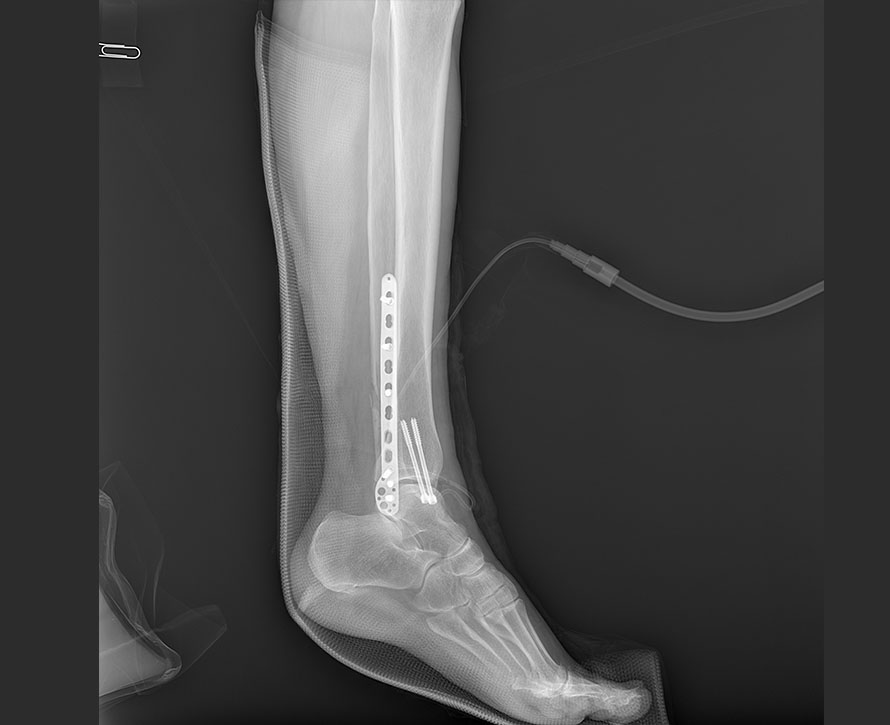

临床图像